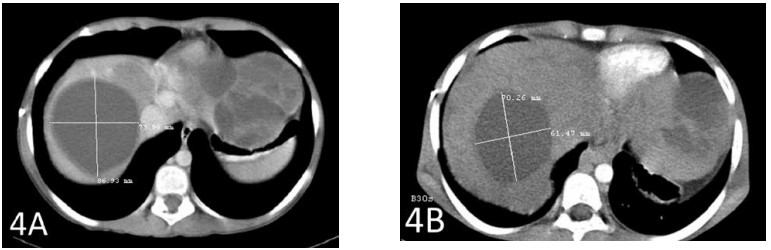

Una TC dopo un totale di 6 settimane di terapia ha mostrato una riduzione di 2 cm della metastasi epatica più grande (Figure 3A e 3B). Anche la seconda metastasi più grande si è ridotta di quasi 2 cm (Figure 4A e 4B).

La Figura 4A mostra la seconda metastasi più grande prima dell’inizio della terapia con DCA IV. La Figura 4B mostra la riduzione del tumore di quasi 2 cm.

Il caso 3 illustra la riduzione del tumore con DCA per via endovenosa in combinazione con IVC ad alte dosi. Questo risultato è stato classificato come malattia stabile secondo la definizione RECIST perché la riduzione del tumore era inferiore al 30%. Sono stati osservati effetti collaterali minimi. Sulla base delle scansioni di octreotide prima e dopo il trattamento, la riduzione delle grandi metastasi epatiche non può essere attribuita alla terapia con octreotide; nessuna delle due scansioni ha mostrato recettori di octreotide nelle metastasi epatiche. Inoltre, la scomparsa dei recettori dell’octreotide dal tumore pancreatico sottolinea ulteriormente la mancanza di benefici legati alla terapia con octreotide. Pertanto, la risposta può essere attribuita alla somministrazione di DCA, in combinazione con farmaci naturali. Con la somministrazione di DCA per via endovenosa si nota talvolta una temporanea riacutizzazione del dolore correlato al tumore, che può essere un segno della risposta del tumore con conseguente infiammazione. Un aumento improvviso della LDH sierica del paziente è coerente con questo effetto. A causa della breve durata della valutazione, non è possibile trarre conclusioni sulla durata della risposta. Gli autori hanno concluso che il DCA per via endovenosa sembra avere un’attività nell’uomo contro il carcinoma pancreatico neuroendocrino.